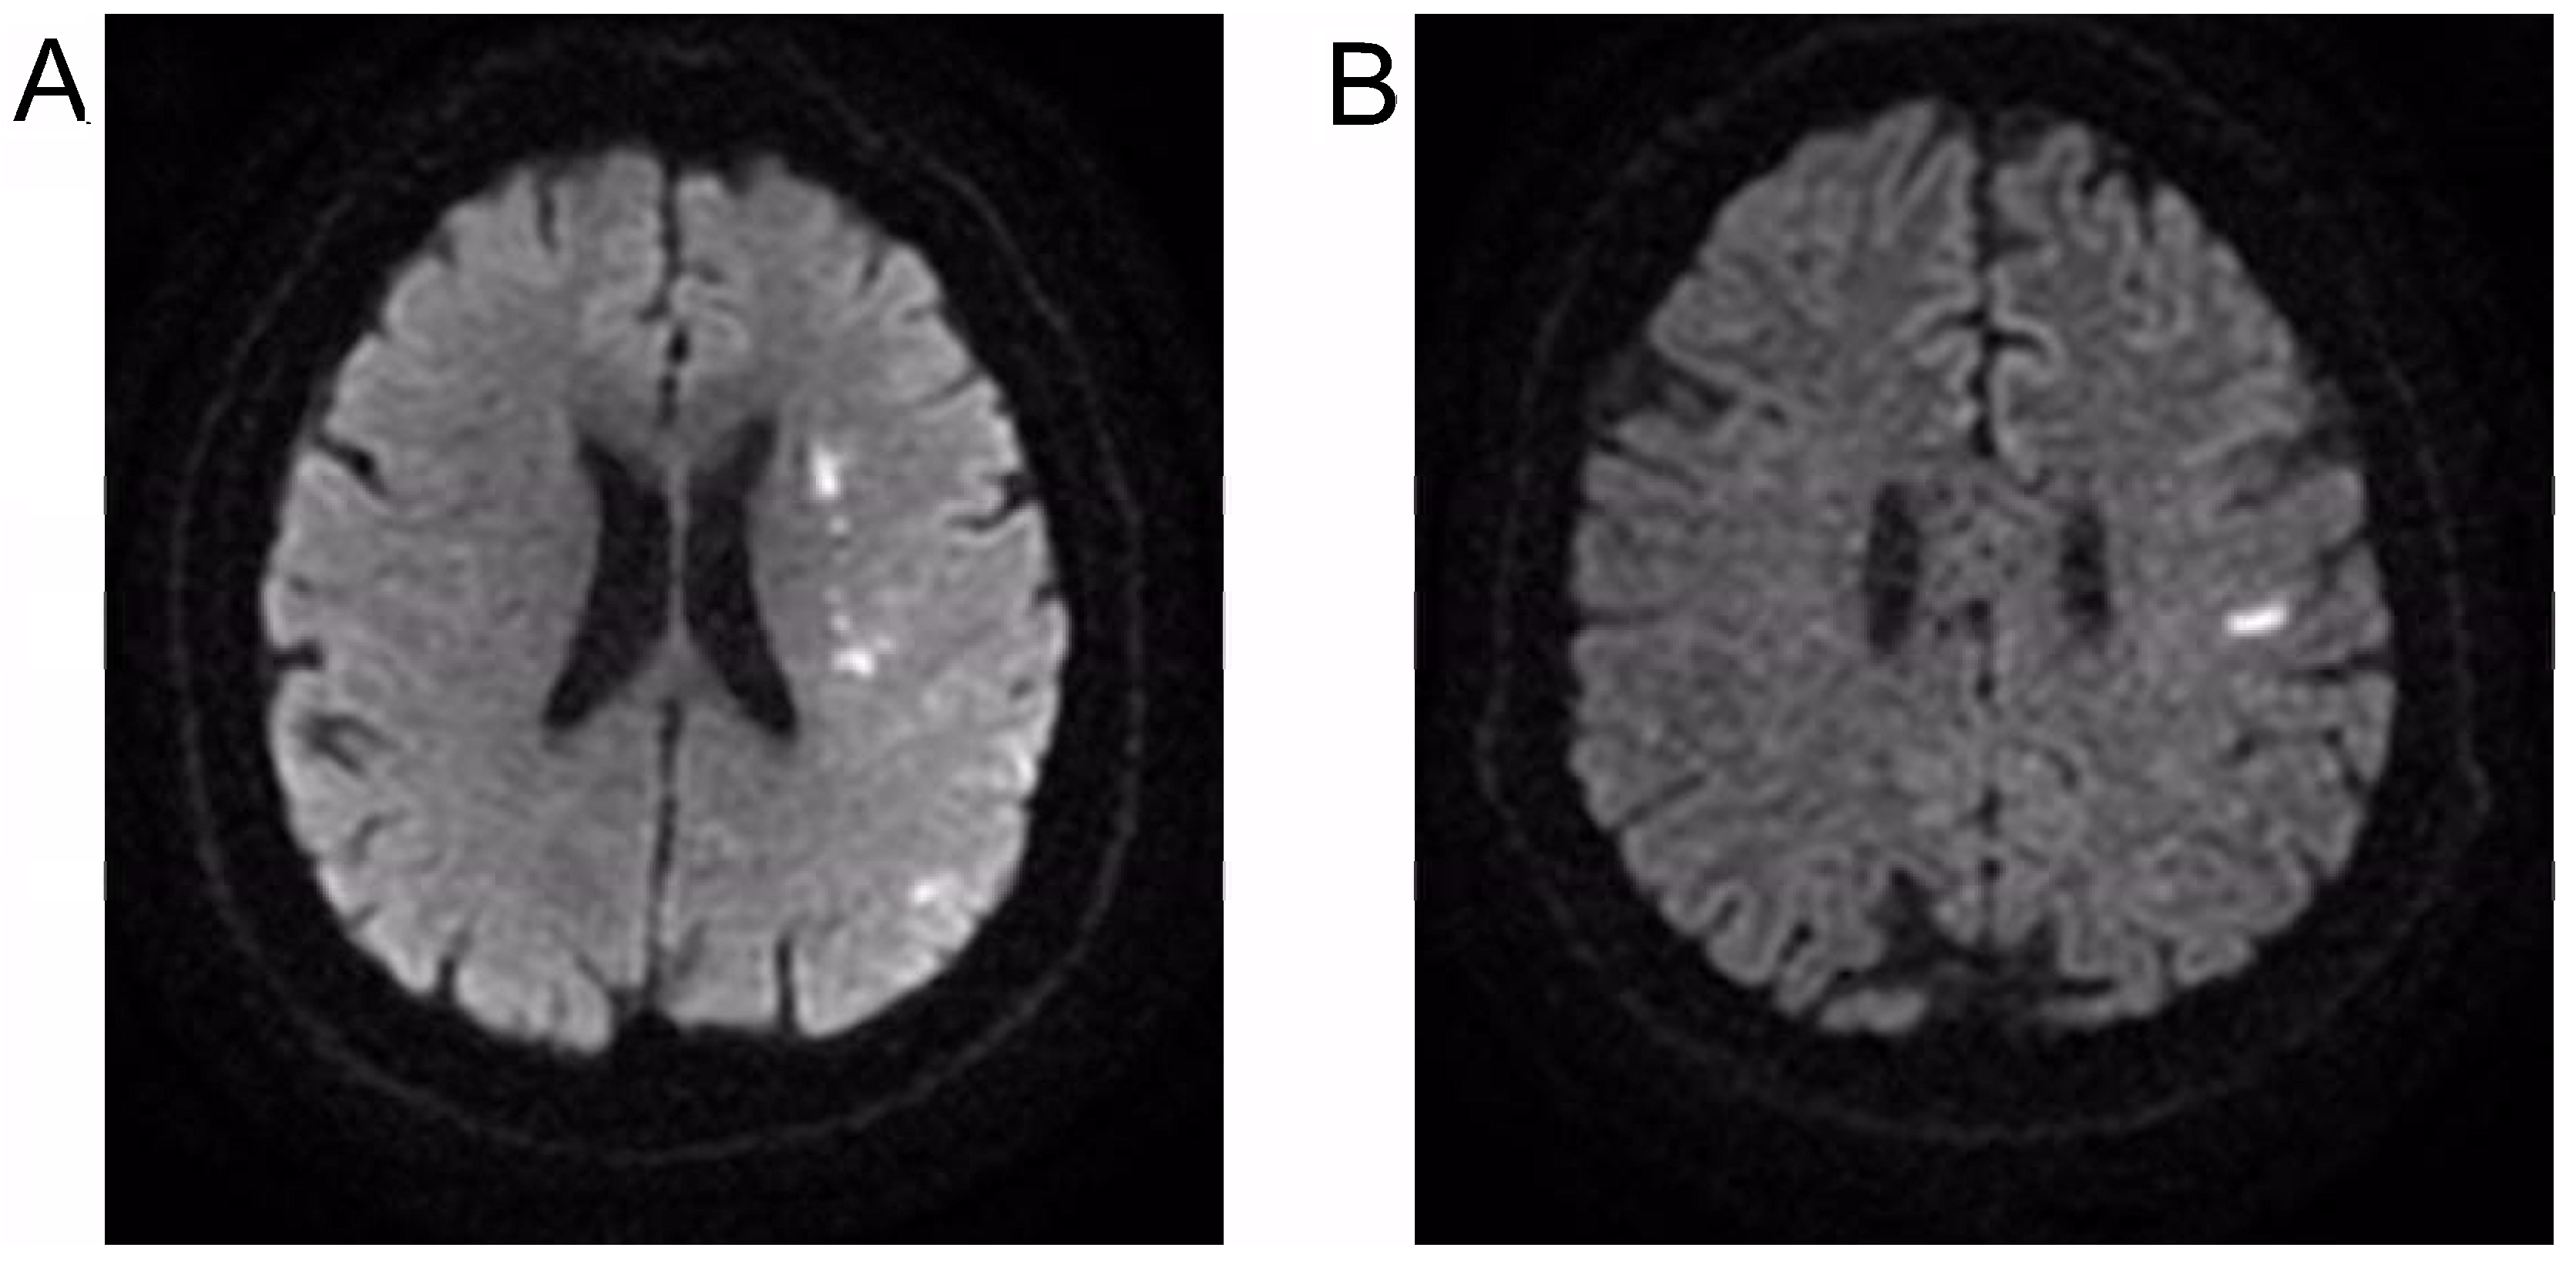

2.2. Neurophysiological Evaluation

2.3. Treatment with NMFES